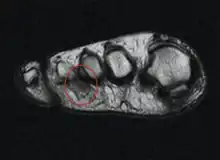

The plantar nerves, with the most common involved location circled.